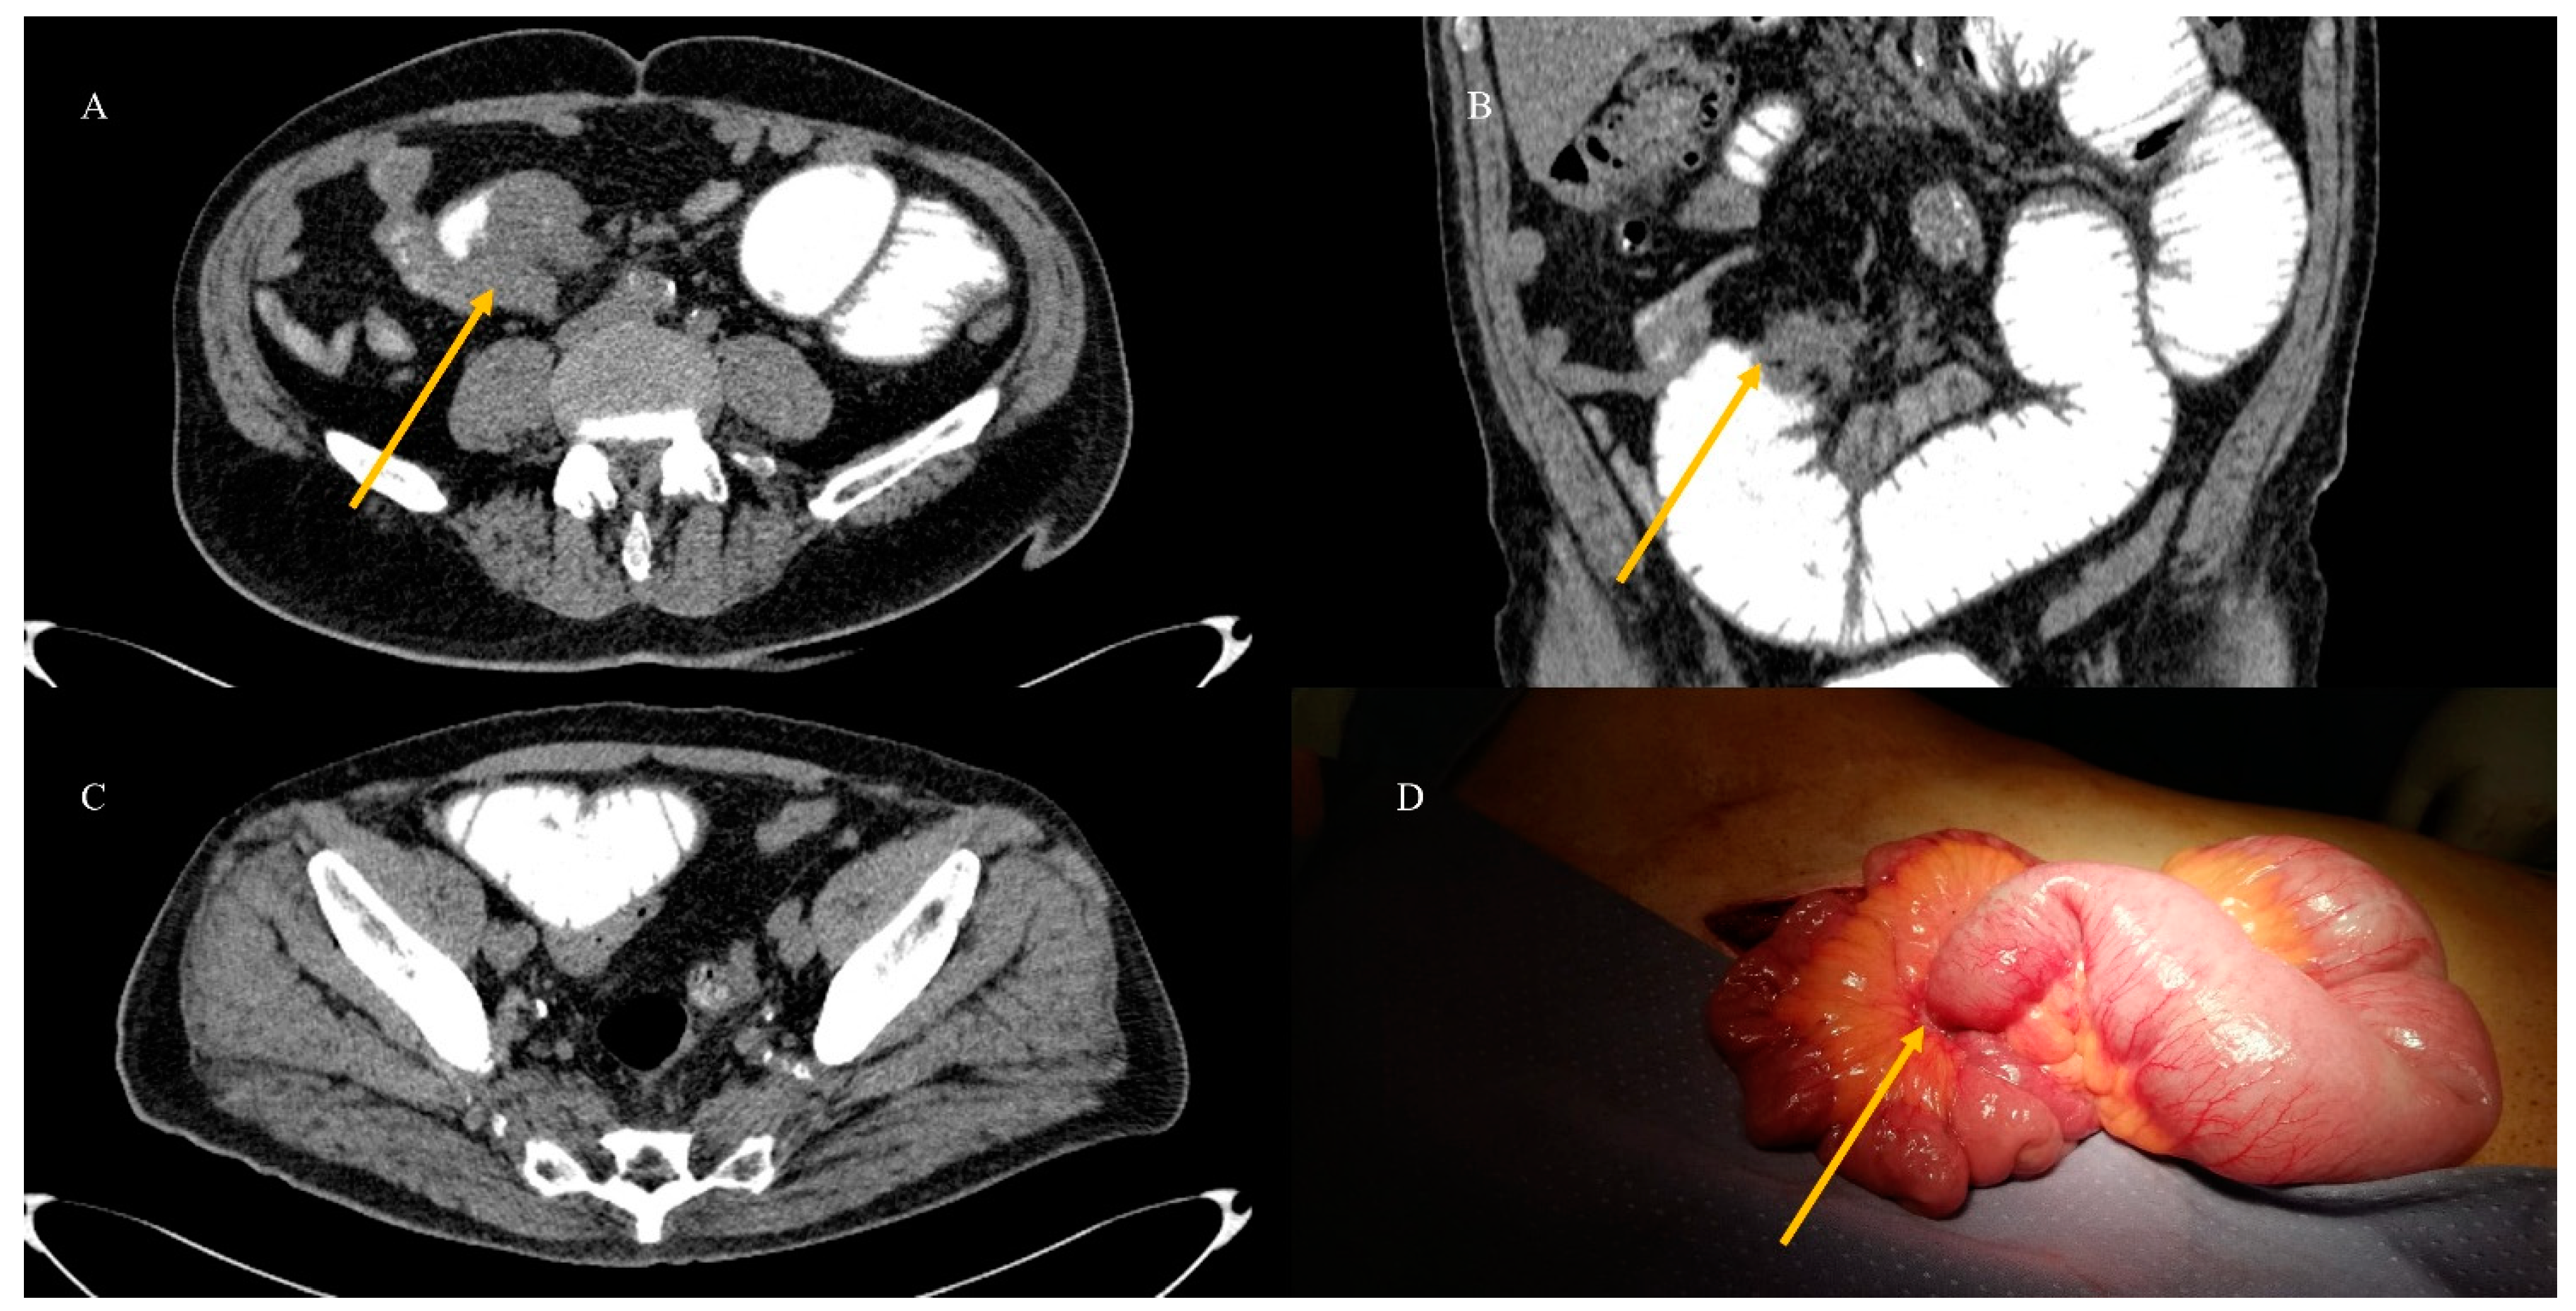

- Tuca, A.; Guell, E.; Martinez-Losada, E.; Codorniu, N. Malignant bowel obstruction in advanced cancer patients: Epidemiology, management, and factors influencing spontaneous resolution. Cancer Manag. Res. 2012, 4, 159–169. [Google Scholar] [CrossRef]

- Alshamsan, B.; Aseafan, M.; Badran, A.; Shaheen, A.; Elshenawy, M.A.; Bazarbashi, S.; Aljubran, A.H. Characteristics and outcomes of small bowel adenocarcinoma: 14 years of experience at a single tertiary hospital in Saudi Arabia. Mol. Clin. Oncol. 2023, 18, 17. [Google Scholar] [CrossRef]

- Kroepfl, V.; Bellotti, R.; Gasser, E.; Esswein, K.; Esser, H.; Kafka-Ritsch, R.; Öfner, D.; Perathoner, A. Small bowel neuroendocrine tumors: An analysis of clinical presentation, diagnostic workup and surgical approach—A single center retrospective study. Front. Surg. 2023, 10, 1072435. [Google Scholar] [CrossRef]

- Basendowah, M.H.; Ashour, M.A.; Hassan, A.Y.; Alshaynawi, S.; Alyazidi, L.K. Multiple small intestinal neuroendocrine tumors with findings of intestinal obstruction. Cureus 2021, 13, e17629. [Google Scholar] [CrossRef] [PubMed]

- Behi, H.; Omry, A.; Dallagi, R.; Changuel, A.; Troudi, D.; Khalifa, M.B. Diagnosing and managing small bowel neuroendocrine tumors presenting as acute obstruction in an elderly patient: A case report and comprehensive management overview. Int. J. Surg. Case Rep. 2024, 122, 110126. [Google Scholar] [CrossRef]

- Nelms, D.W.; Kann, B.R. Imaging modalities for evaluation of intestinal obstruction. Clin. Colon. Rectal Surg. 2021, 34, 205–218. [Google Scholar] [CrossRef]

- Paulson, E.K.; Thompson, W.M. Review of small-bowel obstruction: The diagnosis and when to worry. Radiology 2015, 275, 332–342. [Google Scholar] [CrossRef] [PubMed]